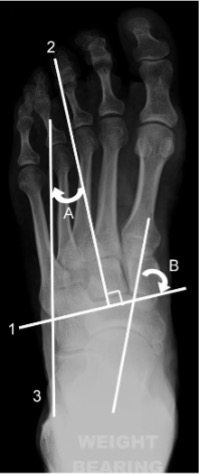

Line 1 = bisection of lesser tarsus

Line 2 = longitudinal axis of lesser tarsus

Line 3 = longitudinal axis of hindfoot

A = lesser tarsus abduction angle

B = talonavicular angle

Longitudinal axis of the lesser tarsus

Perpendicular to a line that transects the lesser tarsus which extends across the tarsus from halfway between the medial aspect of the talo-navicular joint and the medial aspect of the first tarso-metatarsal joint to halfway between the lateral aspect of the calcaneo-cuboid joint and the lateral aspect of the fifth tarso-metatarsal joint.

Lesser tarsus abduction angle

Between the longitudinal axis of the lesser tarsus and the longitudinal axis of the hindfoot.

This angle increases with pronation and decreases with supination.

Talo-navicular angle

Between the midline axis of the talus and the bisection of the lesser tarsus.

Normal: 60-80°

This angle is >80° in the supinated foot and <60° in the

pronated foot.